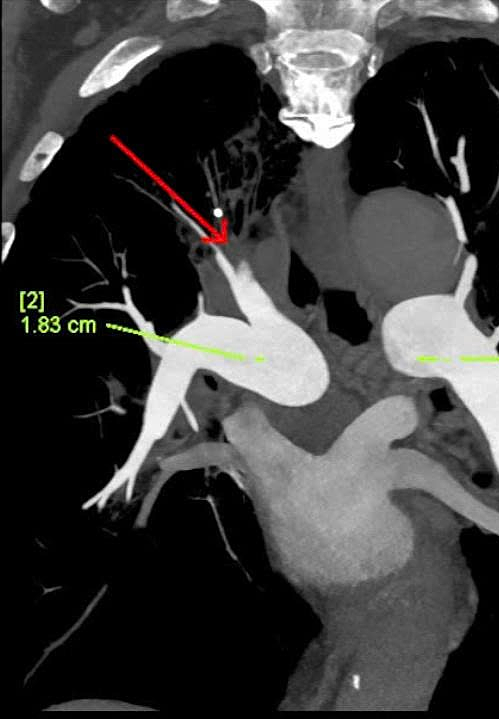

Ông tái khám muộn sau 6 ngày, vẫn còn ho, khó thở giảm nhưng hay mệt. Chỉ số D-Dimer tiếp tục tăng, bác sĩ chỉ định chụp cắt lớp vi tính (CT) Triple Rule Out có tiêm thuốc cản quang, lát cắt siêu mỏng, tái tạo đa thì. Đây là kỹ thuật chẩn đoán giúp đánh giá đồng thời ba nguyên nhân nguy hiểm thường có biểu hiện tương tự nhau là thuyên tắc phổi, bệnh mạch vành và bóc tách động mạch chủ.

Kết quả ghi nhận ông Kiên còn có mảng xơ vữa gây hẹp 50-60% động mạch liên thất trước, xơ vữa dọc thành động mạch chủ, huyết khối lấp hoàn toàn nhánh A1, A2, đoạn xa của một phân nhánh A3 động mạch phổi phải. Bác sĩ xác định người bệnh bị thuyên tắc phổi trên nền COPD cấp bội nhiễm kèm nhiều bệnh lý tim mạch, chuyển hóa. Thuyên tắc phổi không được điều trị kịp thời sẽ gây gián đoạn dòng máu đến phổi, dẫn đến thiếu oxy toàn thân, tụt huyết áp, rối loạn nhịp tim, ngừng tim.